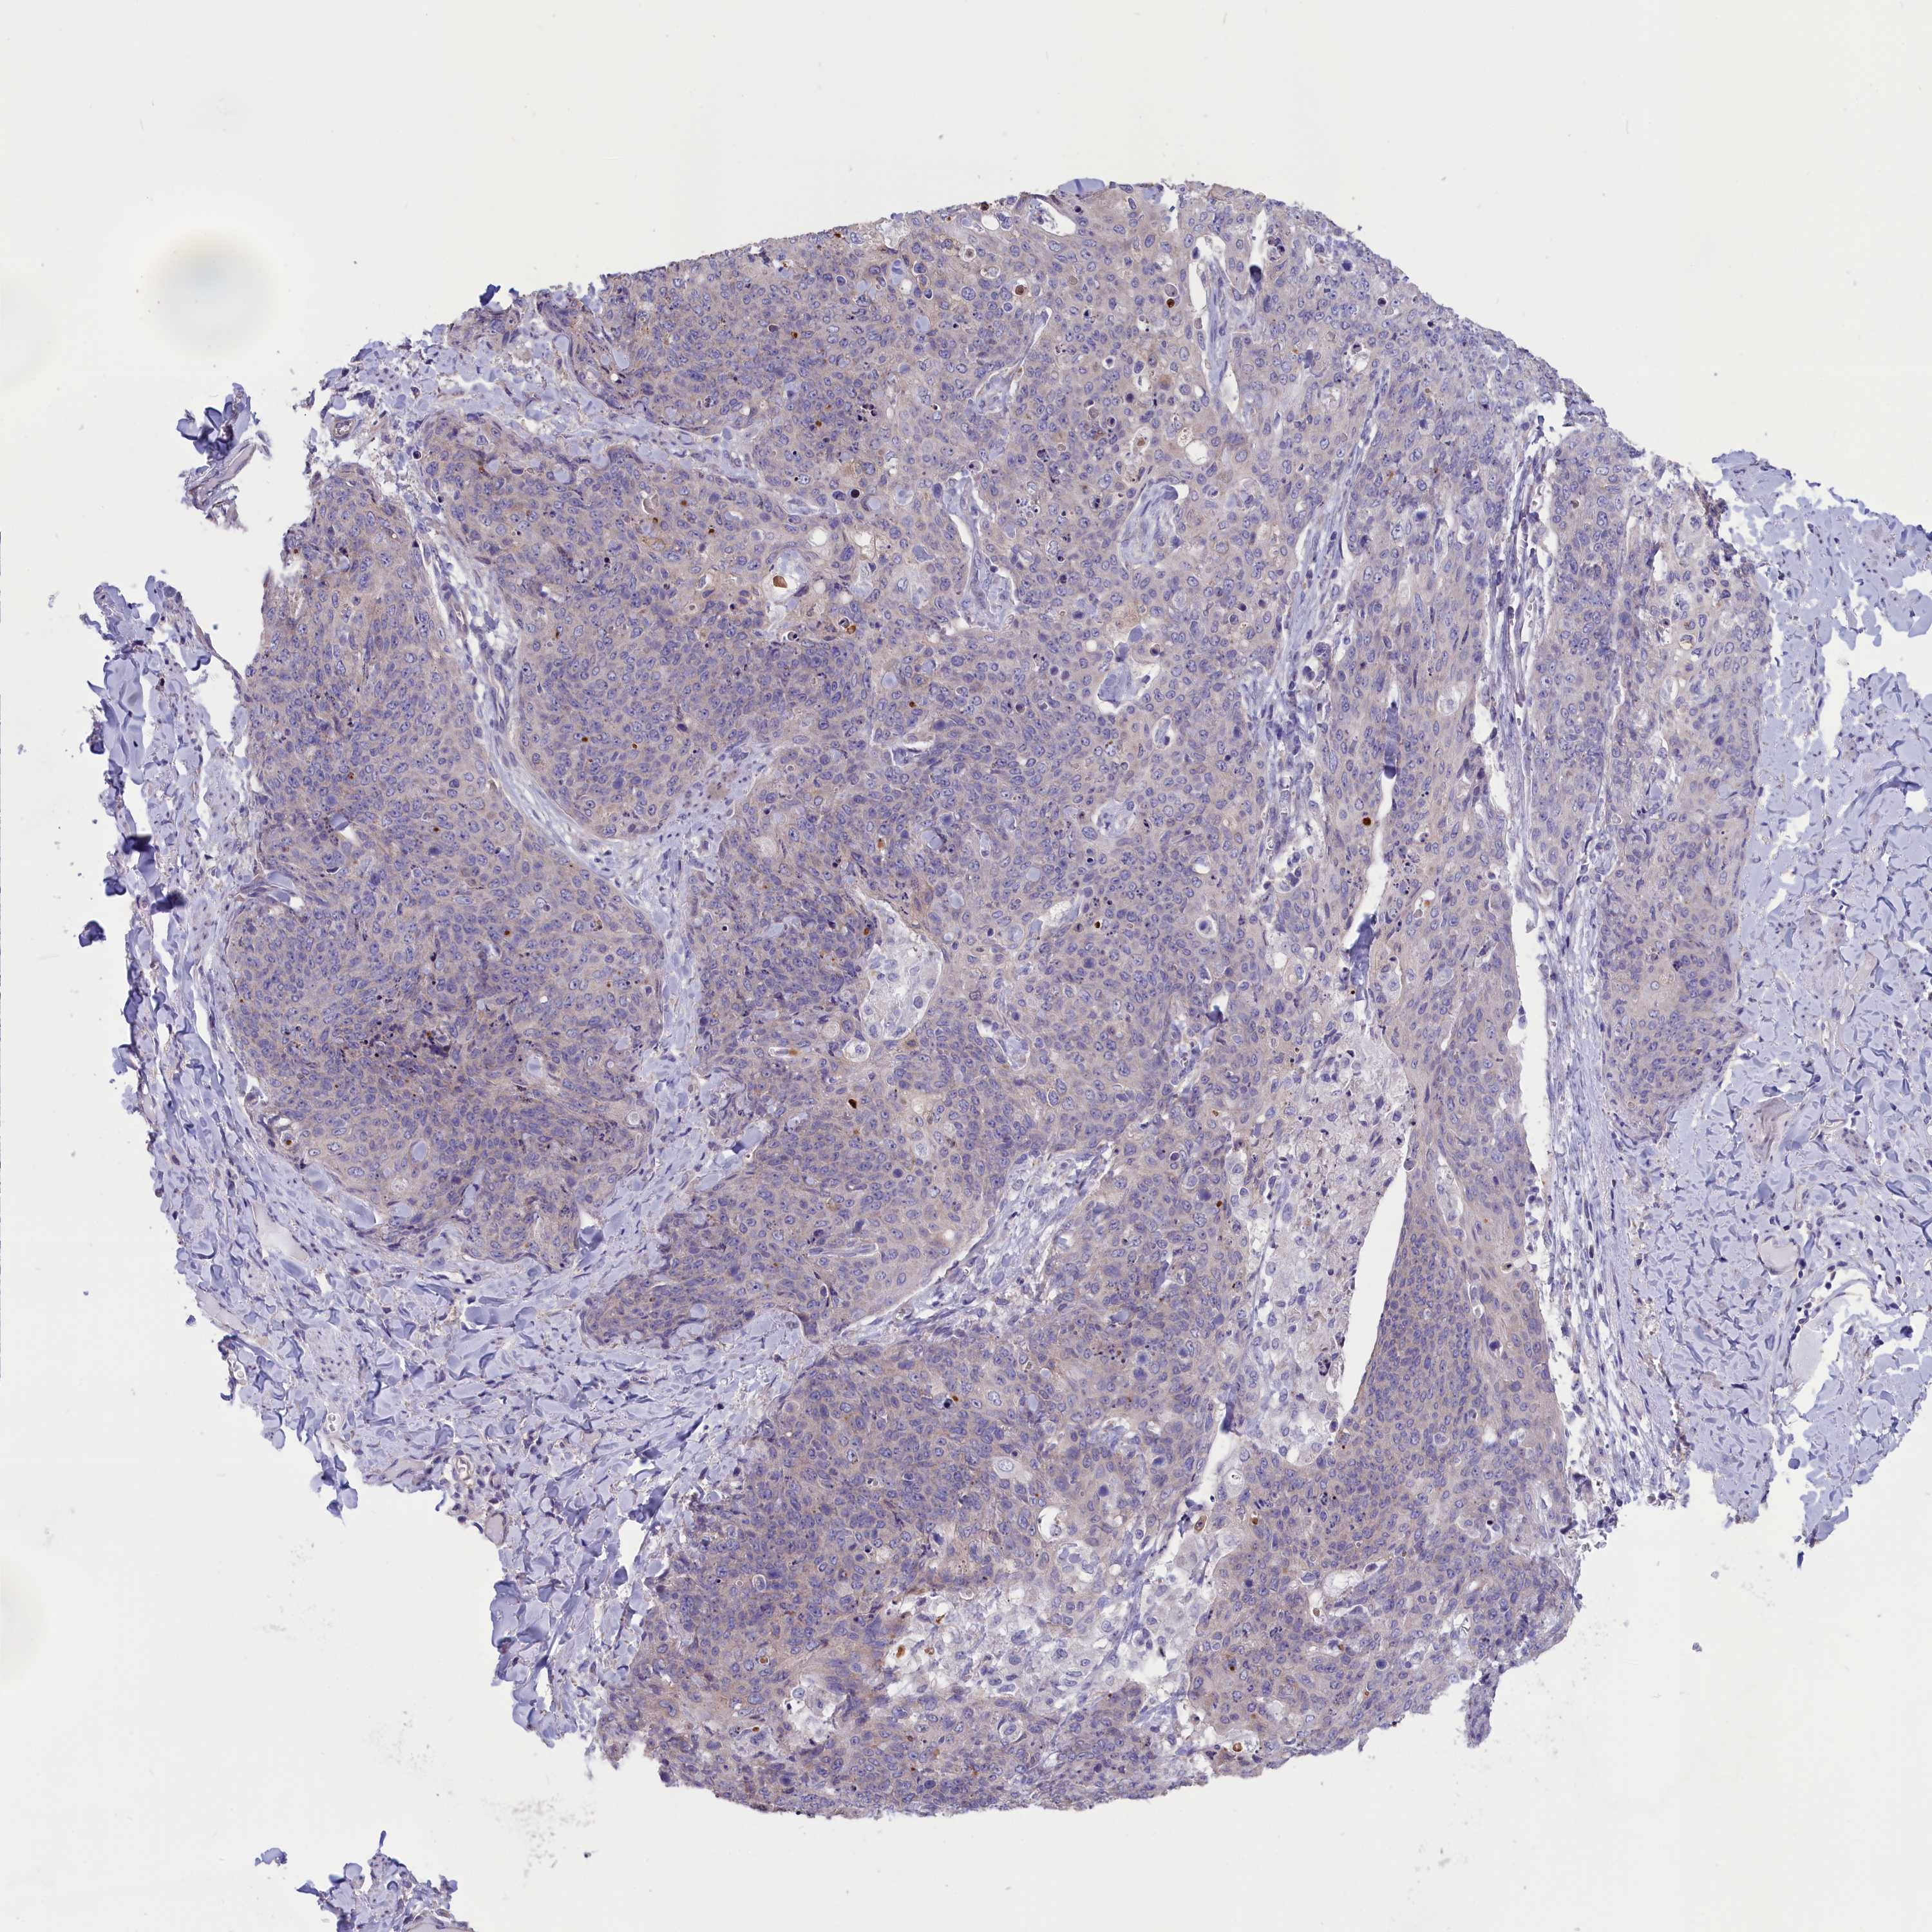

SKIN CANCER - Protein expressioni

A mouse-over function shows sample information and annotation data. Click on an image to view it in a full screen mode. Samples can be filtered based on level of antibody staining by selecting one or several of the following categories: high, medium, low and not detected. The assay and annotation is described here.

Each image is clickable and will lead to virtual microscopy that enables deeper exploration of all samples and also displays staining intensity scores, fraction scores and subcellular localization as well as patient and tissue information for each sample.

Staining

Low

Moderate

Weak

<25%

Cytoplasmic/membranous

Squamous cell carcinoma, NOS